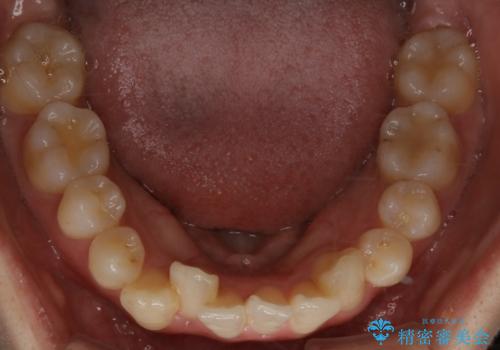

- 前歯のガタつきと噛み合わせの改善を主訴に初診来院され、審査の結果マウスピース装置による非抜歯での矯正を行うこととなりました。

元々の顎骨や口腔・歯槽骨が小さく、どうしても歯が並びきらない状況になっていました。マイクロインプラントという固定源からゴムかけを行うなど、補助装置を活用しながら臼歯部を順番に遠心方向(奥)に移動させていくことで抜歯をしなくても歯が並ぶよう計画を立てました。

歯のガタつきを治すため矯正治療を希望。審査の結果、非抜歯での矯正が可能であるという見通しが立ったためインビザラインによる非抜歯矯正治療を行った。

歯を並べるスペースを作るために、歯の遠心移動と歯列の拡大、歯自体を少しだけ小さく削る(IPR)という方法を複合的に組み合わせて配列を行いました。遠心移動用のゴムかけにはマイクロインプラントという小さいネジを用いて骨に直接固定源を求めました。